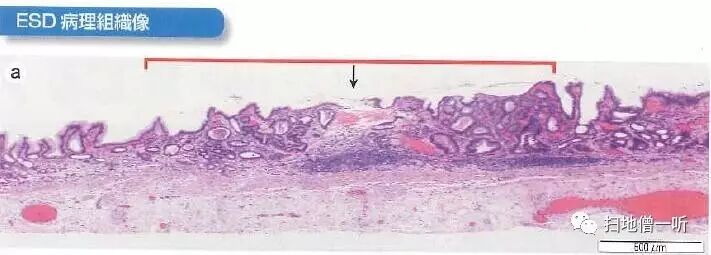

箭头处为自发出血处。高倍镜下可见高分化管状腺癌腺体。

最终病理诊断:

胃角小弯,O-IIc,2mm,tub1,T1a (M),UL(-)